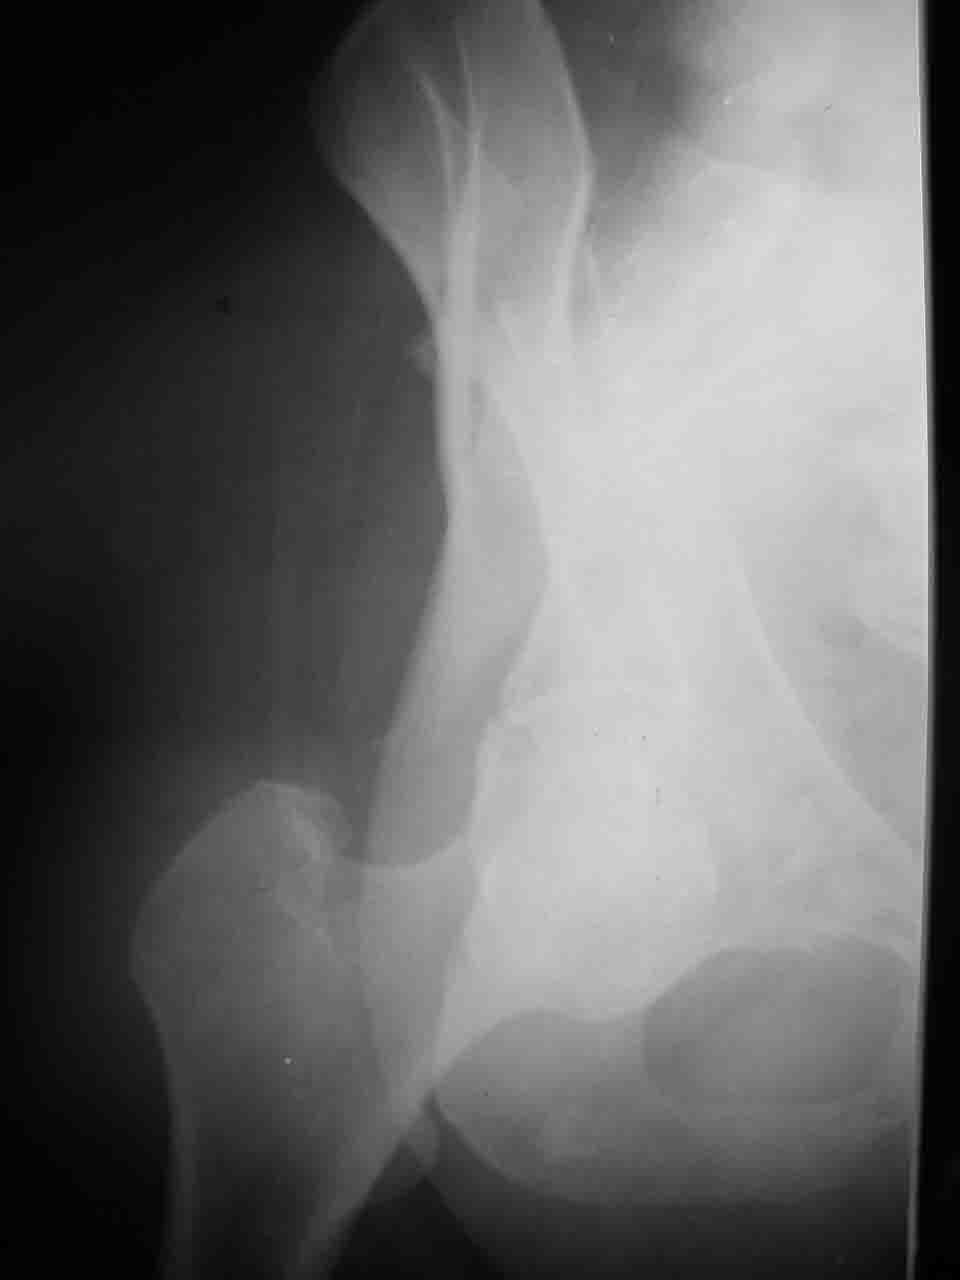

Интерес к реконструкции вертлужной впадины у меня появился довольно-таки давно, но до недавнего времени как-то не ощущалась готовность к практической реализации, а местный подход достаточно консервативен - перелом срастется,

а далее будет видно. Такую точку зрения я не разделяю, поэтому через конференции,ортофорум и свои случаи пытаюсь практически и теоретически *продвинуть* для себя тему реконструкции вертлужной впадины.

Логика подсказывает, что все-таки лучше иметь анатомически полноценную впадину, хотя ранее упоминалось состояние вторичной конгруэнтности и одно наблюдение у меня есть, когда у больного с полностью нарушенной анатомией впадины и подвывихом головки бедра кзади и кверху боли отсутствовали при относительно достаточном для стиля жизни больного объёме движений. Но это только одно наблюдение и кроме перелома впадины у этогобольного была и тяжелая ЧМТ в анамнезе. Основываясь на формулировке структуры ацетабулюм Э. Летурнеля - как перевернутой буквы Y, впадина для полноценной функции сустава должна иметь сферичность, соответствующую размеру головки бедра и если один из компонентов в дефиците, то функциональные последствия рано или поздно проявятся.

Сложностью, ассоциативностью характера перелома, я бы с радостью воспользовался мининвазивной перкутанной фиксацией винтами, но боюсь, что результат был бы ещё хуже, техникой непрямой репозиции перелома не владею, поэтому пытаясь получить анатомичную впадину приходится широко открывать, по крайней мере пока, а дальше буду пытаться уменьшать пространство...

Илеофеморальный доступ не совсем передний и сравнительно с илеоингвинальным, и Кохера-Лангенбека открывает весь наружный таз кроме самых передних отделов лонных костей, фиксацию которых я не ставил в задачу. Обширность диссекции, большая длительность операции и более высокий риск гетерооссификации - отрицательные моменты в обмен на возможность легче ориентироваться.

Комбинированные доступы - хорошая альтернатива, меньший процент осложнений, но я заметил , что без сбора *мозаики* безымянной кости сложно отрепонировать переднюю колонну, а с нерепонированной передней колонной невозможно анатомично собрать заднюю колонну и соотв. фрагменты стенки - так.что все равно открывать придется широко. Поэтому выбирая комбинированный

подход, передний доступ должен был бы быть продлен до задней трети крыла безымянной кости, а задний - практически до того же уровня, оставляя 6-7 см мостик. При этом вместо одного послеоп. рубца у больного остаются два сравнительно длинных.

Вопрос доступа к вертлужной впадине при остеосинтезе задача не простая. Конечно, у Летурнеля и Тайла всё давно описано, нам остается только брать на вооружение. Но сами понимаете, что не бывает двух одинаковых ситуаций, поэтому в каждом случае вопрос решается сугубо индивидуально. Наша главная цель - восстановить анатомию с нанесением минимальной дополнительной травмы тазобедреннному суставу, думаю с этим никто не поспорит. Расширенный илиофеморальный доступ уж слишком травматичен (как сказал один коллега "таз лежит отдельно, больной отдельно").Стоит ли делать из пациента анатомический препарат для того чтобы легче ориентироваться. Да и нужно ли собирать всю "мозаику"? Мы применяли при таких операциях своеобразную операционную хитрость - сначала устраняли грубое смещение крыла под гребнем с фиксацией так называемой "плавающей" пластиной (временно фиксированной на двух винтах)- доступ или продлевали боковой, или делали небольшой дополнительный разрез над гребнем. Это позволяло устранить грубое смещение и захождение отломков тела повздошной кости, что значительно облегчало репозицию и остеосинтез впадины над сводом. Основное внимание конечно же уделяли нагружаемому задне-верхнему отделу. Сообщите ваш адрес, пришлю схемы и рентгенограммы.